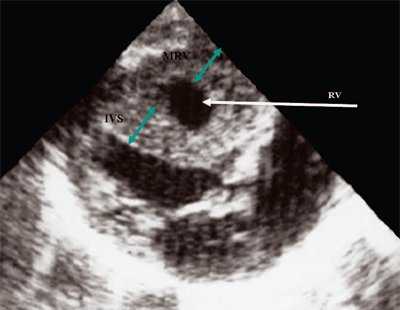

Характерными особенностями выраженной объемной перегрузки правого желудочка являются дилатация желудочка, при которой толщина миокарда не превышает верхней границы нормы, увеличение правого предсердия, парадоксальный характер движения межжелудочковой перегородки и увеличение амплитуды движения трикуспидального клапана (рис. 2, 3).

Рис. 2. Длинная ось сердца. Объемная перегрузка правого желудочка при дефекте межпредсердной перегородки. Объем сброса крови превышает 200% МОС. Отмечается выраженная дилатация правого желудочка.

Рис. 3. Объемная перегрузка правого желудочка при дефекте межпредсердной перегородки. В- и М-сканирование. Стрелкой показан парадоксальный характер движения межжелудочковой перегородки.

Для левого желудочка признаком объемной перегрузки являются увеличение полости левого предсердия и желудочка, а также экскурсии межжелудочковой перегородки и миокарда задней стенки левого желудочка (рис. 4).

Рис. 4. Объемная перегрузка левых отделов сердца. В- и М-сканирование. Отмечается усиление экскурсии межжелудочковой перегородки и миокарда задней стенки левого желудочка.

IVS - межжелудочковая перегородка, MLV - миокард левого желудочка, LV и RV - левый и правый желудочек.